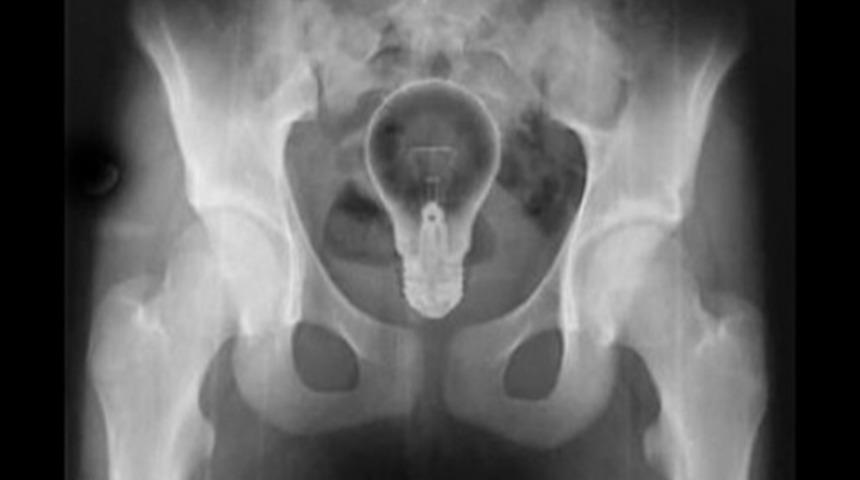

Bu pek parlak bir fikir gibi durmuyor. - - - - - -

Danua cinsi bu köpek 43,5 adet çorap yemeyi başarmış.